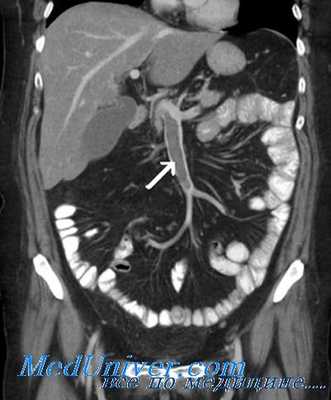

Компьютерная томография - КТ.

Чувствительность метода составляет 65-85%.

С помощью этого исследования можно выявить тромб в просвете портальной вены, нарушения структуры печени, варикозно-расширенные вены пищевода и желудка.

При комбинировании этого метода с допплеровским ультразвуковым исследованием можно обнаружить обструкцию портальной вены.

Проводится также КТ-портография. На снимках тромбоз портальной вены визуализируется как участок пониженной плотности в просвете портальной вены, периферия которого определяется как зона повышенной плотности. Кроме того, у пациентов с портальной гипертензией можно обнаружить сеть коллатералей, варикозно-расширенные вены.